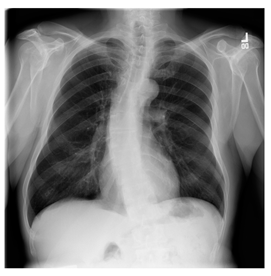

- (c)

- NIH Database

ANIH is an X-ray type image database collecting chest medical images. Some samples are shown in Figure 12c.

Figure 12.

Sampled images in the tested benchmark databases: (a) Breast-MRI-NACT-Pilot (breast), (b) ACRIN-DSC-MR-Brain (brain), (c) NIH (chest), (d) Lung-PET-CT-Dx (lung), (e) Prostate-MRI (prostate), and (f) Other grayscale standard images.